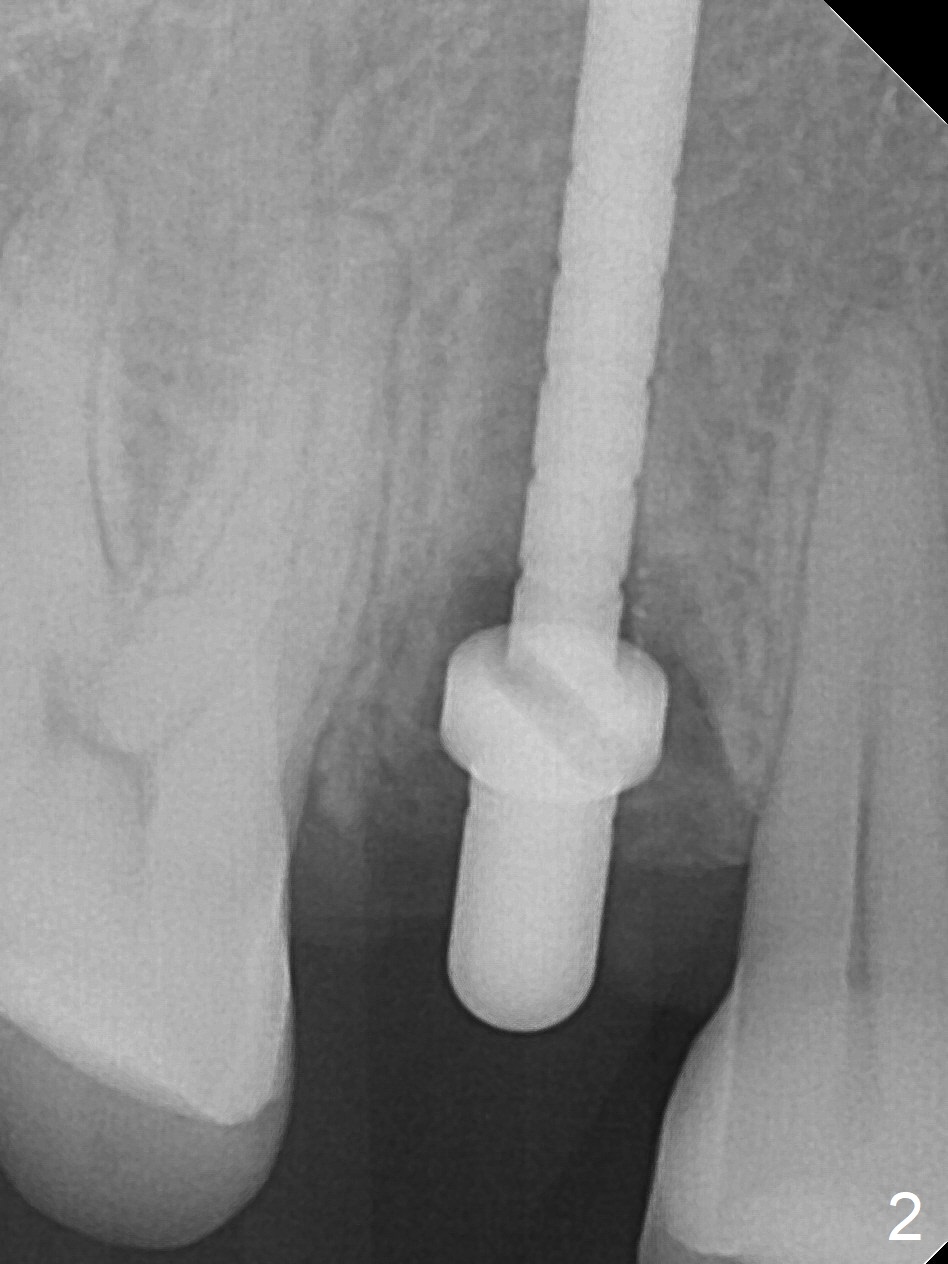

After extraction of residual root at #4 with mesiopalatal subgingival margin (Fig.1), the mesiopalatal crestal bone loss is noted. Instead of the mesial slope, the initial point of the osteotomy is at the mesial and middle (buccopalatally) of the socket bottom (Fig.2, 2'). The initial depth with 2 mm drill is 20 mm (gingival level), while the last drill (3 mm) is used for 17 mm (because of soft bone). When a 3.8x16 mm implant is placed (Fig.3,4), the distal gap of the socket is closed, suggesting that the implant moves to the least resistant area. However, it is favorable to the mesial crestal defect (Fig.4). The buccopalatal position of the abutment (4.5x4(4) mm) is a little too palatal (Fig.5, taken prior to provisional fabrication). The implant seems to have osteointegrated 6 months postop (Fig.6).